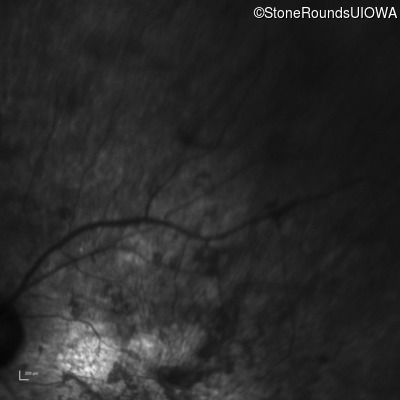

Infrared Fundus Photograph - Right - Hand Motion 1' sc

Exemplar